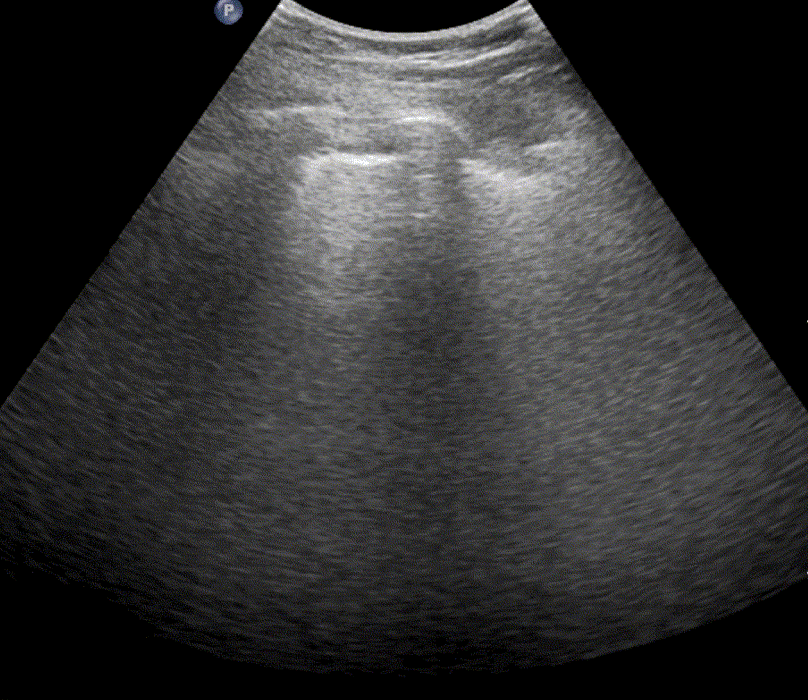

In healthy, air-filled lungs, the ultrasound image appears gray. This occurs because air scatters sound waves as they encounter solid interfaces such as the pleura, resulting in a diffuse, speckled gray appearance beneath it. Within normal lung parenchyma, there is minimal acoustic impedance mismatch to reflect the ultrasound beam; instead, the beam is absorbed by air within the alveoli. Consequently, in a normal lung ultrasound, the parenchymal texture is not visualized. The only visible structure is the pleural line — a bright, horizontal echo that moves synchronously with respiration.

Position the probe within an intercostal space and adjust its angle and placement until the “batwing sign” becomes visible. This sign appears when the acoustic shadows of the ribs and the bright pleural line together form a pattern resembling a bat’s wings. The presence of this sign confirms correct probe positioning and orientation for lung ultrasound examination.

Ribs

Ribs are visualized as hyperechoic, curved lines that cast acoustic shadows beneath them, obscuring the underlying structures.

Pleura

On ultrasound, the pleura appears as a bright, horizontal echogenic line. For optimal visualization, reduce the imaging depth to approximately 5 cm and position the pleural line at the center of the image.

A-lines

A-lines are highly echogenic, horizontal reverberation artifacts that appear parallel to and equidistant beneath the pleural line. They result from repetitive reflection of the ultrasound beam between the pleura and the probe, producing regularly spaced bright lines on the image.

The presence of A-lines indicates a normally aerated, air-filled lung. They are typically observed when imaging at a depth of 9–11 cm, and are most distinct when the ultrasound beam is perpendicular to the pleural surface.